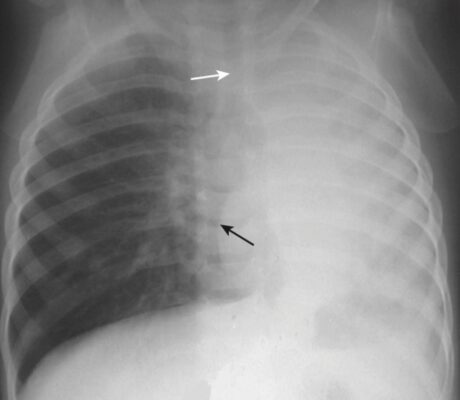

- Trong xẹp phổi do tắc nghẽn, một hoặc tất cả các cấu trúc này sẽ dịch chuyển về bên phổi mờ (về phía bên bị mất thể tích) (Hình 3).

- Khi tích tụ đủ dịch màng phổi, tràn dịch lượng lớn sẽ “đẩy” các cấu trúc di động ra xa và có một sự dịch chuyển của tim và khí quản ra khỏi bên bị mờ (Hình 4).

- Nửa phổi bị mờ đục bởi vì phổi không còn chứa không khí, nhưng không có lực kéo về phía bên bị viêm phổi do giảm thể tích cũng như không có lực đẩy ra khỏi bên bị viêm phổi do tràn dịch lượng lớn. Không có sự dịch chuyển của tim hoặc khí quản.

- Có thể có hình ảnh phế quản chứa khí (Hình 6).